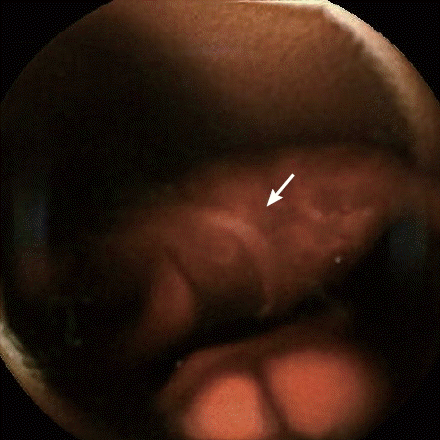

A 46-year-old male complaining of edema for 2 months and exertional dyspnea and chest pain for 2 weeks was admitted to our hospital. The patient denied abdominal pain, nausea, and loss of appetite. He had no history of diabetes mellitus, hypertension, or malignancy. Initial laboratory studies showed that his hemoglobin level was 11.1 g/dl. Urinalysis revealed yellow urine with proteinuria 7,588 mg per day. CT angiogram (CTA) of lungs showed multiple pulmonary embolism (

Fig. 1CT angiogram showing multiple pulmonary embolism.